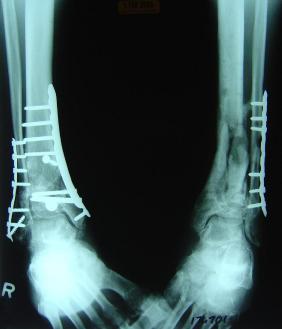

Pre-corrective surgery X-Rays of the damaged right & left legs / ankles

These x-rays were taken at Dr Armendariz’s office, just prior to performing any corrective surgery. As can be seen in these images,

there was no tibia bracing provided by Dr. Keller. Liam was released from Dr Keller’s care with instructions that full weight bearing could

be accomplished within 2 months of Keller’s last surgical procedure. The best example to examine is the second image (from the left) of the

top how. Notice how the bones that should be aligned with the tibia are in fact on the other side of the leg. The third image shows how badly

Liam’s left foot was twisted as a result of the pool placement of the external fixation. What is not obvious is that the screw at the bottom

of the plate on the right fibula missed being screwed into the plate.